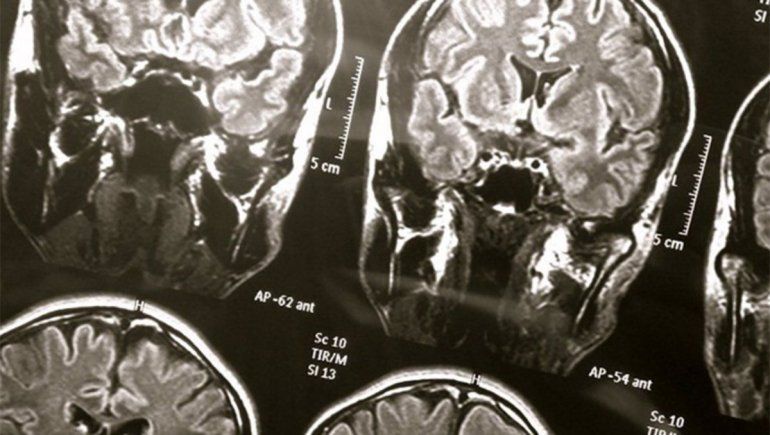

El hombre había ingresado en el servicio de urgencias de un hospital tras sufrir una caída que le provocó una hemorragia cerebral, y posteriormente se deterioró. Cuando los médicos le realizaron un electroencefalograma (EEG), descubrieron que el paciente había desarrollado epilepsia. Sin embargo, durante las grabaciones del EEG había sufrido un ataque al corazón y había muerto.

El equipo afirma que el análisis de las grabaciones de los 30 segundos anteriores y posteriores a que el corazón del hombre dejara de latir sugiere que en sus últimos momentos experimentó cambios en diferentes tipos de ondas cerebrales, incluidas las alfa y las gamma. El estudio sugiere que las interacciones entre los diferentes tipos de ondas cerebrales continúan después de que la sangre deja de fluir en el cerebro.